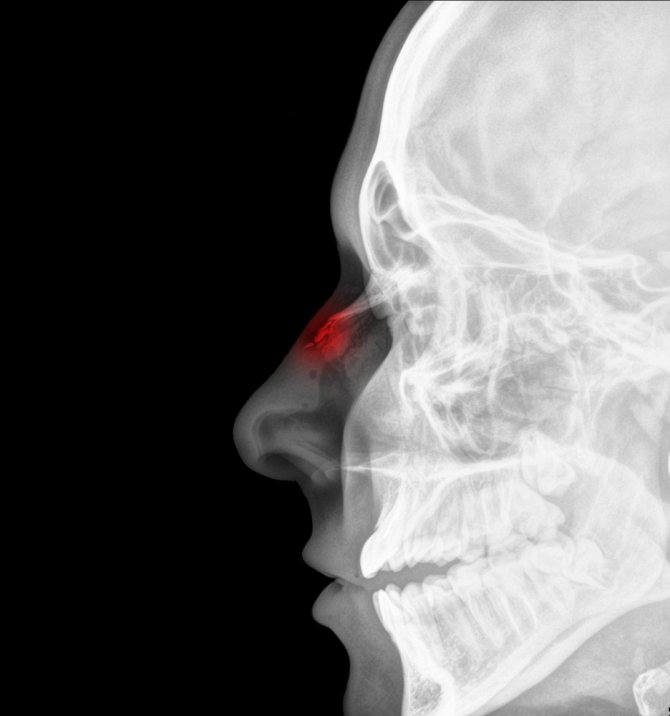

Инфицирование считается одним из самых опасных осложнений, существенно затрудняющих и затягивающих заживление поврежденного органа. Если при этом были травмированы костные ткани черепа, мозговые оболочки, то высока вероятность развития менингита. Последствия могут быть самыми плачевными — вплоть до смертельного исхода! При сильном кровоизлиянии в область глазного яблока возможны нарушения зрительной функции и даже полная слепота.

Наиболее опасным осложнением после перелома носа считается инфицирование. В этом случае восстановление существенно затянется. Если травма также затронула кости черепа и мозговые оболочки, то может развиться менингит. Последствия могут быть довольно плачевными, возможен даже летальный исход. При сильном кровоизлиянии в область глазного яблока может наступить слепота. Если своевременно оказать пострадавшему медицинскую помощь, развития этих неприятных последствий вполне можно избежать.

Еще стоит отметить наличие аномального размера зрачка, он не реагирует на свет, у пациента снижается зрение, возникают сложности с дыханием. При рассматривании любого объекта может наблюдаться раздвоение. Это симптом, который получил название «двойное зрение». Возникает оно в результате того, что на глазодвигательные мышцы оказывает давление отек. Нередко зрение может исчезнуть полностью.

Когда орбиты глаз находятся в окружении кровоподтеков, которые симметричны, то это явление получило название симптом очков. Это говорит о том, что имеет место сотрясение мозга. Если возникло обильное выделение крови из носа, то это признак перелома основания черепа. Для диагностики необходимо провести МРТ и КТ.